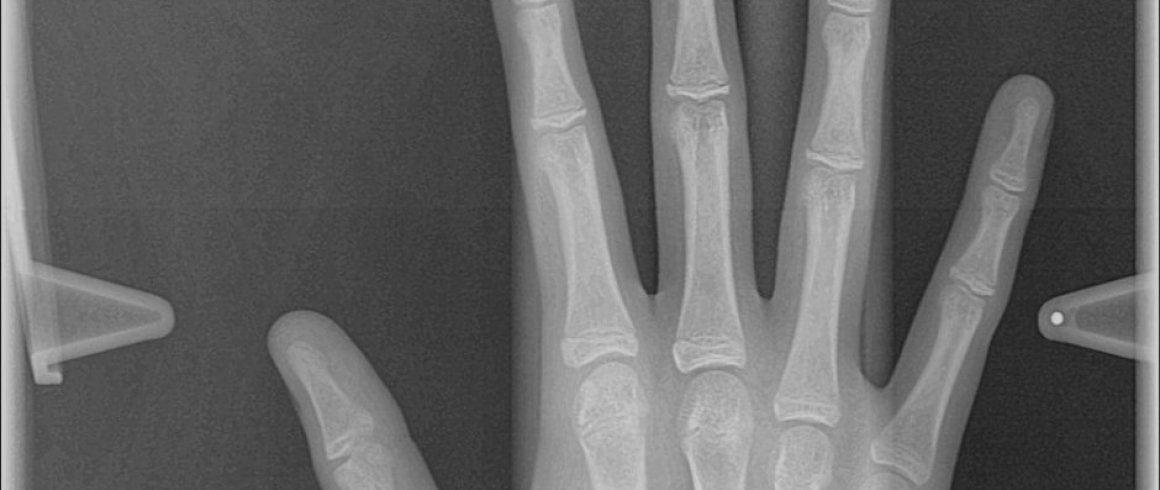

- Carpal

- Edad Ósea